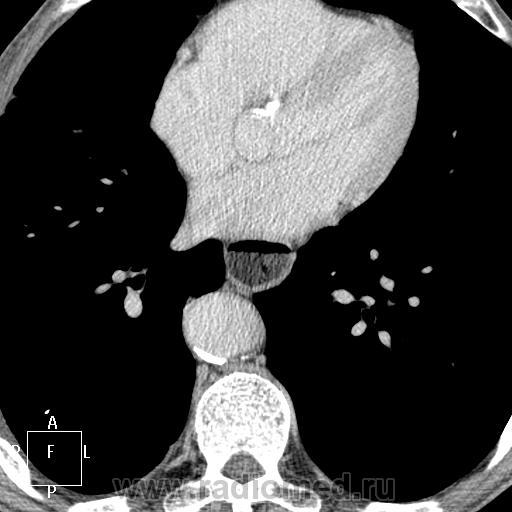

Отсроченная фаза (120 сек), пищевод:

В области анастомоза накопление контраста до 100 ед.Н, в более проксимальных отделах пищевода накопление стенкой нормальное, до 45 ед.Н.